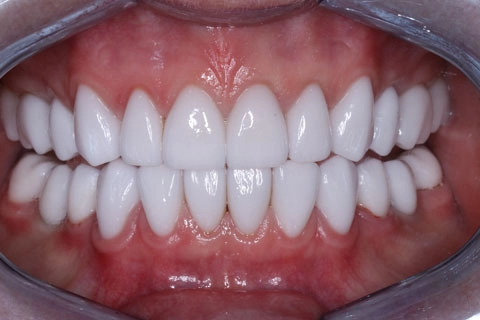

Проведена ортопедическая реабилитация.

Фронтальная группа зубов верхней и нижней челюстей – установлены виниры из литий дисиликата.

Жевательная группа – восстановлена коронками из диоксида циркония, в том числе 3.6, 4.6 – коронки на имплантатах.